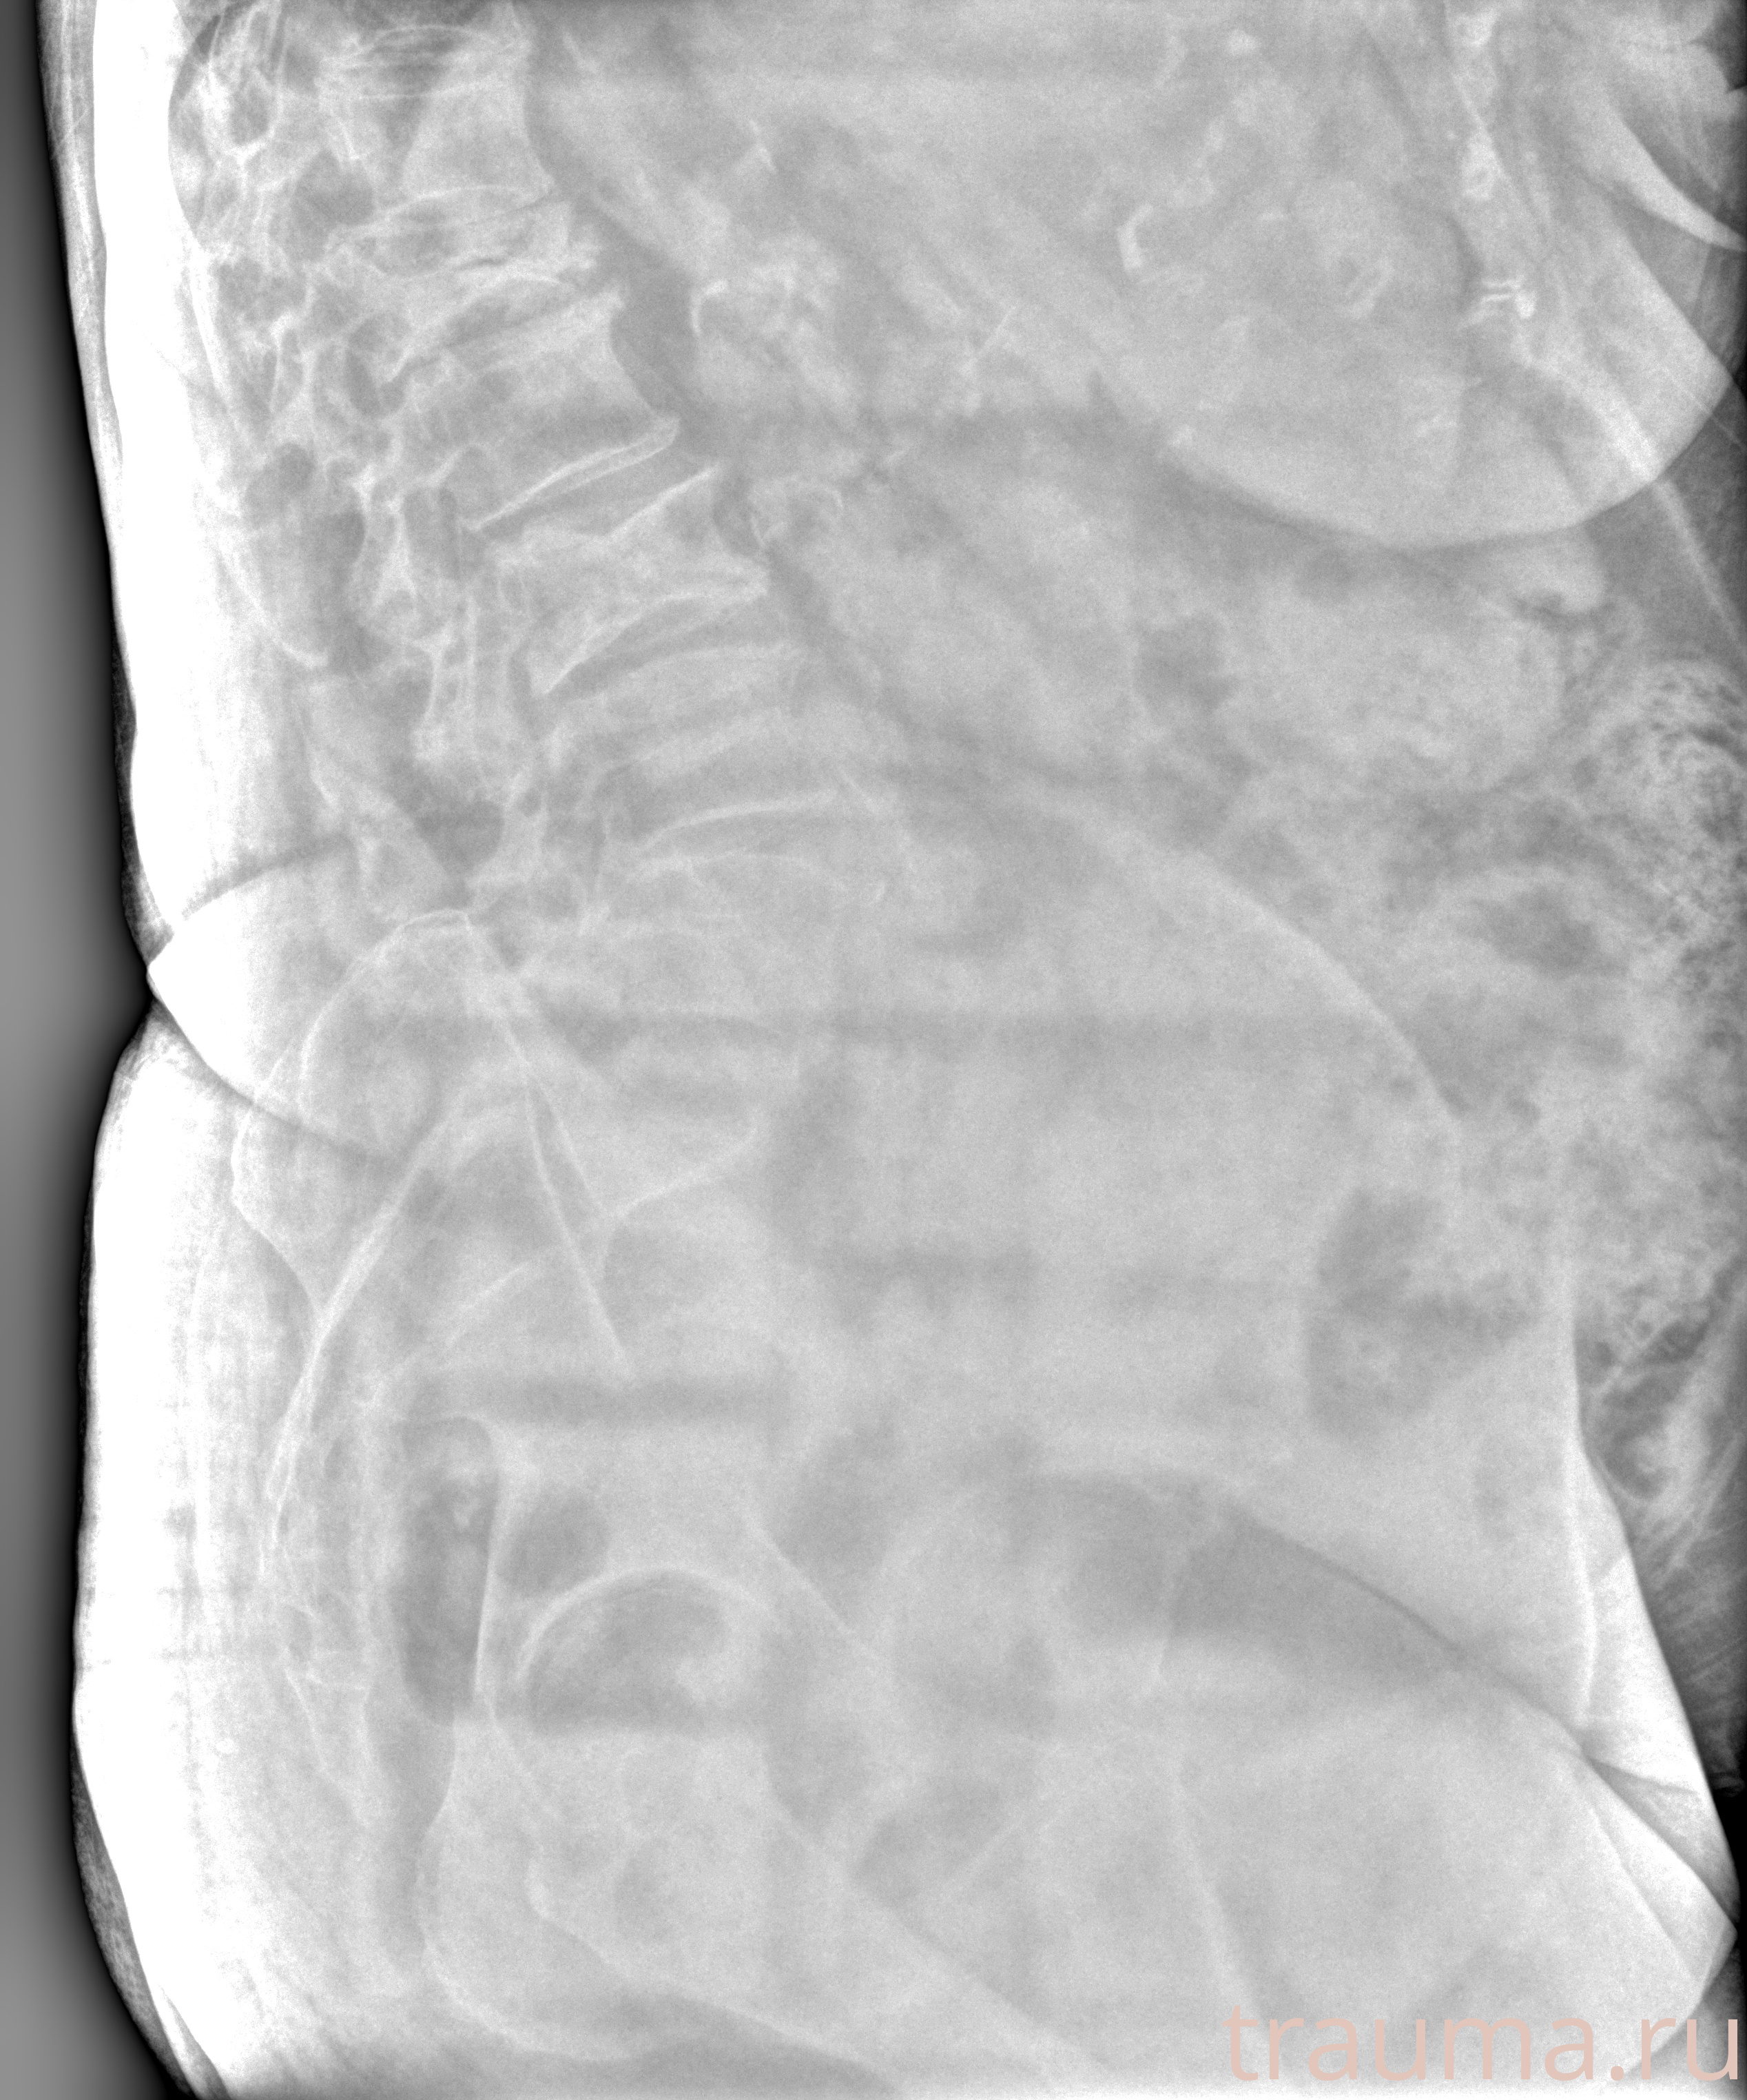

Рентген на дому: по вашему адресу приезжает врач-рентгенолог, травматолог-ортопед с мобильным рентгеновским аппаратом, проводит диагностику травмы или заболевания, делает необходимые рентгенограммы, дает рекомендации по дальнейшему лечению. Получить качественные снимки в домашних условиях возможно благодаря уникальной методике, разработанной МосРентген Центром для института  Склифосовского